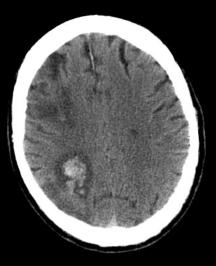

A complication of old cerebral infarcts is that they can rebleed as is the case here. The edema associated with large infarcts can compress local small blood vessels. As the edema subsides, reperfusion of the damaged vessels can lead to hemorrhage.

Here is another patient who had a thrombotic infarct 2 weeks prior to this CT and now presents with new cognitive deficits.

What do you think happened?

The degree of effacement here is consistent with an infarct that occurred at least a few days prior.